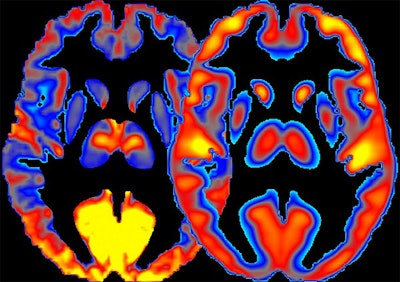

Combining the FDG-PET and fMRI allowed the group to identify regions of the brain where glucose metabolism exceeded the underlying brain activity. These "high-cost" regions, characterized by low brain activity, were associated with increased alcohol consumption.

New imaging technique combines measures of brain activity (left) with glucose absorption (right). Image courtesy of Dr. Ehsan Shokri-Kojori."In heavy drinkers, we saw less regional power ... in the thalamus, the sensory gateway, and frontal cortex of the brain, which is important for decision-making," first author Dr. Ehsan Shokri-Kojori said in a statement. "These decreases in power were interpreted to reflect toxic effects of long-term exposure to alcohol on the brain cells."